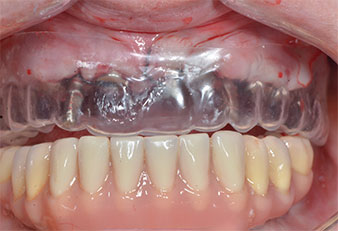

Хирургичен водач

Фиг. 9 Хирургичен водач осигурява достатъчно пространство на съществуващата протеза да служи за временна, закрепена върху временните импланти.